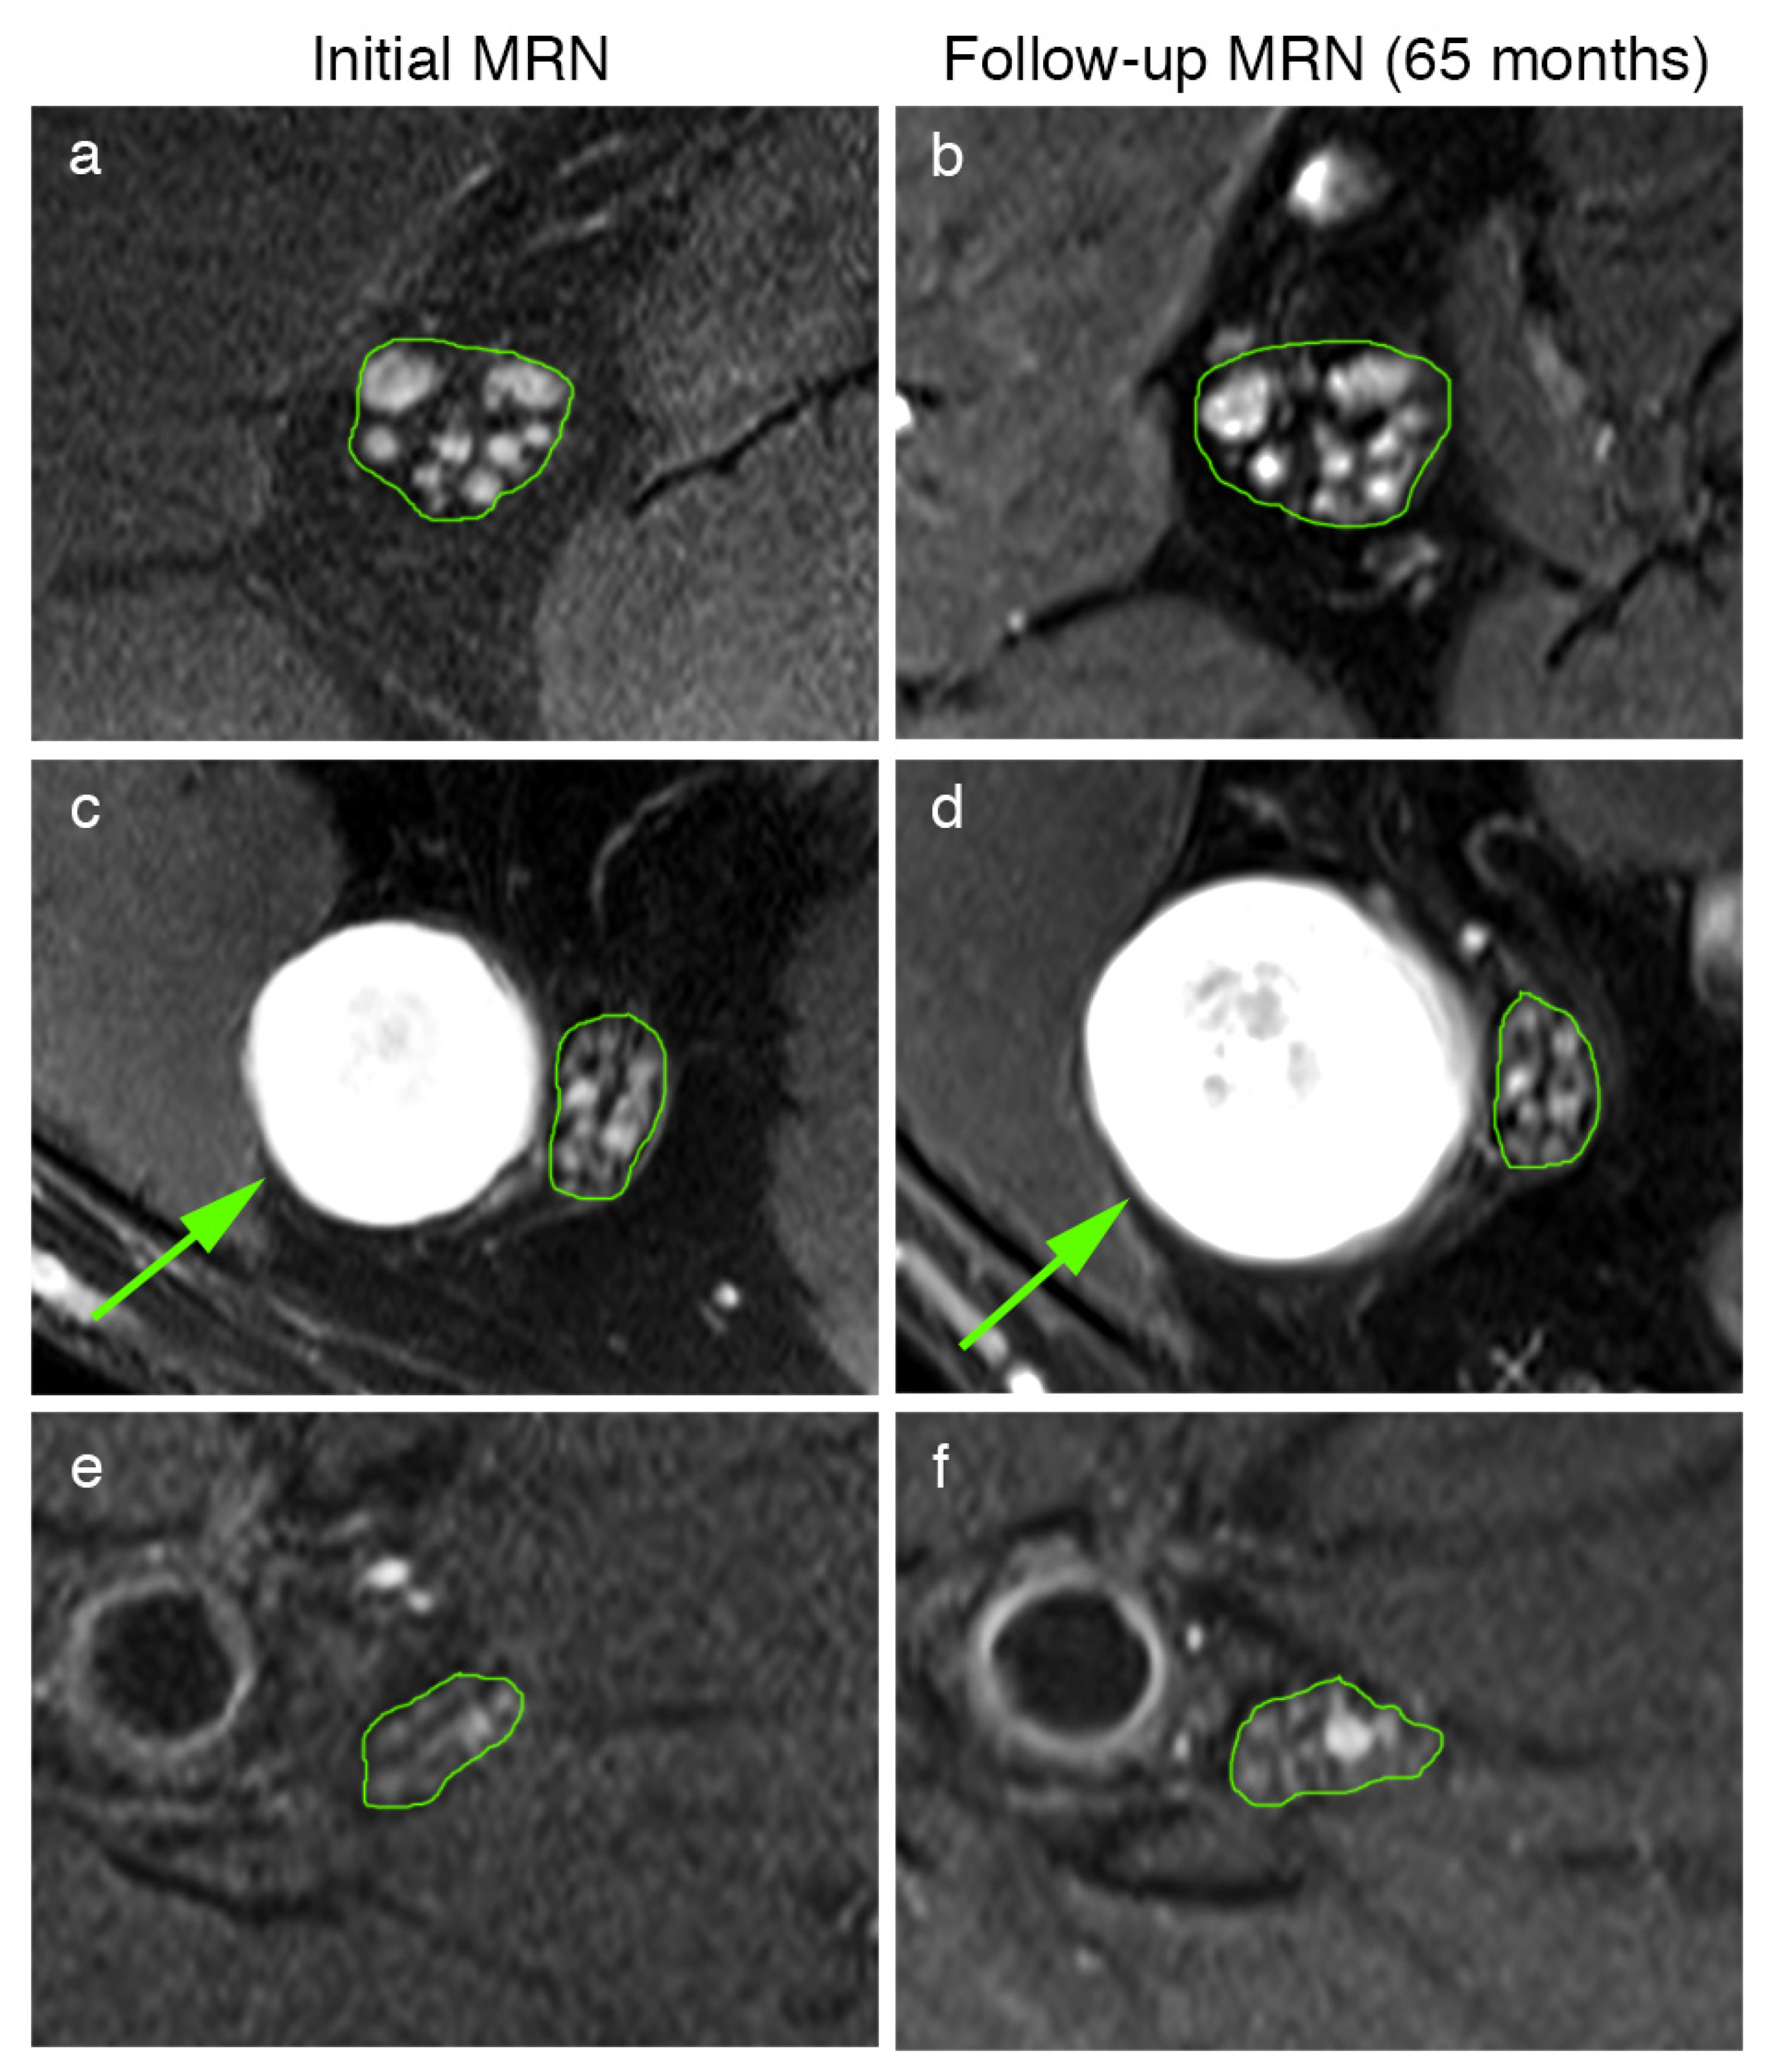

Moreover, the peripheral nerve lesion count and lesion diameter were quantitatively assessed for nine schwannomatosis patients in the initial and follow-up examination (Table 1, Figure 3). This analysis revealed that peripheral nerve lesion count did not differ in follow-up examinations for microlesions (total count: 544 vs. 533, 60.33 ± 61.42 vs. 59.22 ± 59.56, p = 0.34), intermediate lesions (total count 12 vs. 19, 1.33 ± 4.00 vs. 2.11 ± 5.60, p = 0.19), or macrolesions (total count 8 vs. 9, 0.89 ± 2.67 vs. 1.00 ± 3.00, p = 0.35). The diameters of the nerve lesions were decreased in follow-up MRN for microlesions (1.08 ± 0.29 mm to 1.03 ± 0.28 mm, p < 0.01), did not differ for intermediate lesions (2.67 ± 0.36 mm to 2.56 ± 0.49 mm, p = 0.87), and increased for macrolesions (10.63 ± 2.90 mm to 13.72 ± 3.66 mm, p < 0.01).

Figure 3.

Representative MRN images at different levels of the initial (a,c,e) and follow-up MRN examination (b,d,f) of patient 7’s sciatic nerve at the proximal thigh level (a,b). Multiple microlesions present at the initial MRN (a) show no dynamic change in either their number or their diameter after 65 months (b). At the distal thigh level, a solitary macrolesion (arrow in (c,d)) was observed within the peroneal portion of the sciatic nerve (c), which was significantly larger in the follow-up (d), whereas adjacent microlesions within the tibial portion remained unchanged (c,d). In contrast to the high number of microlesions at the thigh levels, these nerve lesions were only occasionally observed at the calf level (e,f).